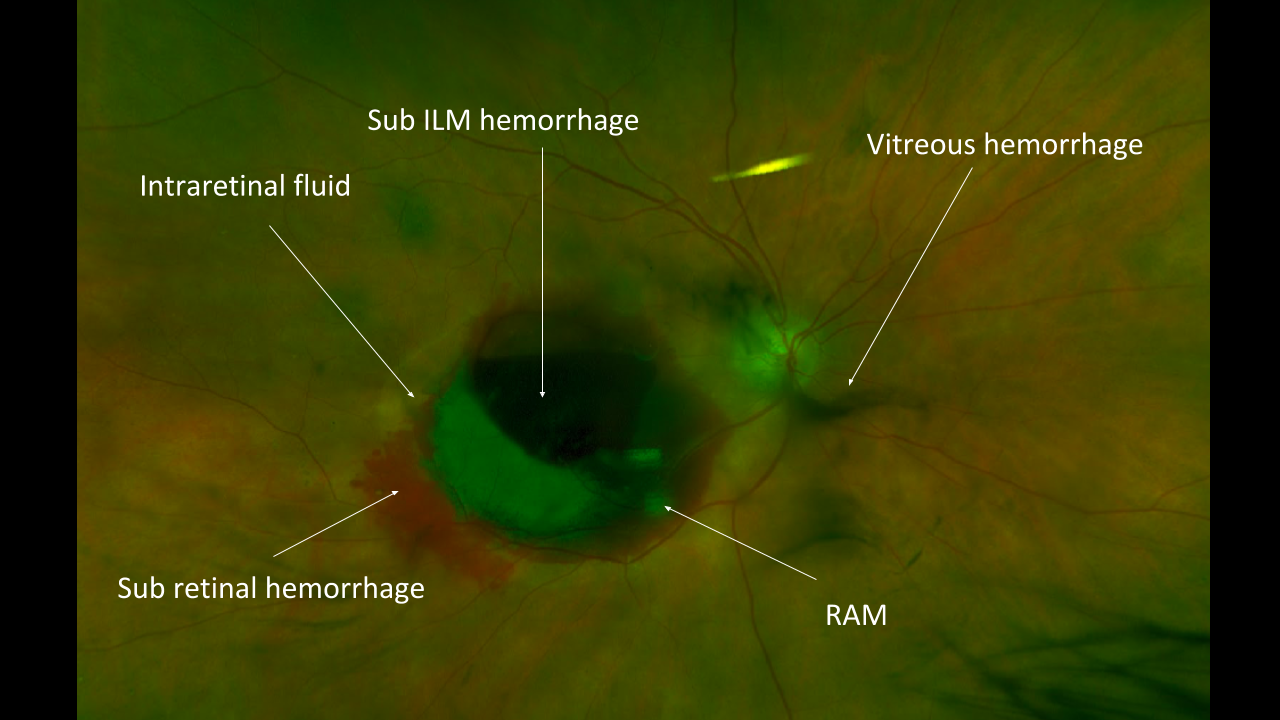

Get the next level OCT learning experience: video analysis with expert commentary, including an extensive case discussion, deep insight, and clinical pearls.

Diagnostic Confidence

Our searchable atlas contains over 100 must-know cases. Grow your knowledge in all areas of eye disease: retina, glaucoma, pediatrics, anterior segment, neuro, pathology, oculoplastics, and ocular emergencies.